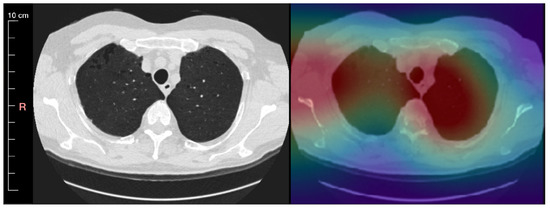

- Muşat, B.; Andonie, R. Semiotic Aggregation in Deep Learning. Entropy 2020, 22, 1365. [Google Scholar] [CrossRef]